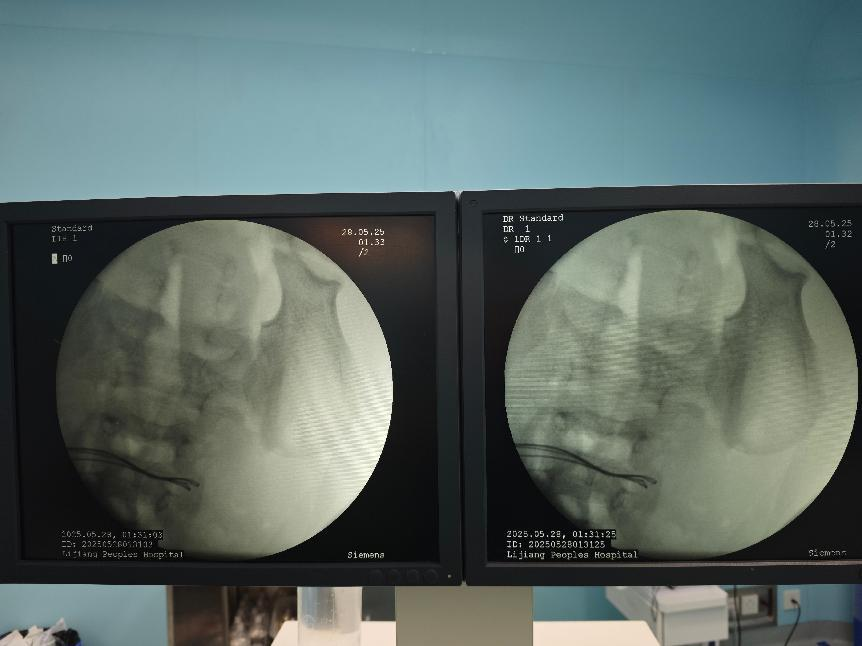

術(shù)中取出小腸異物

經(jīng)過研判,醫(yī)療團(tuán)隊(duì)?wèi){借著精湛的技術(shù)和堅(jiān)定的信念,克服了重重困難,成功取出了該病人體內(nèi)的37顆磁力珠,并對穿孔部位進(jìn)行了細(xì)致的修補(bǔ)。經(jīng)過數(shù)小時(shí)的緊張手術(shù),通過腹腔鏡、內(nèi)的聯(lián)合操作,讓病人脫離了生命危險(xiǎn)。

術(shù)中完善床旁DR見腹腔內(nèi)已無異物